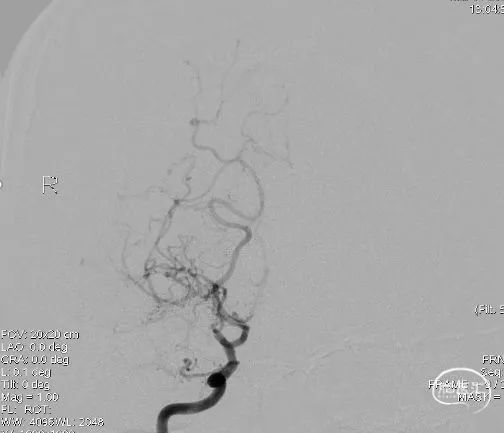

术前右颈总动脉侧位: